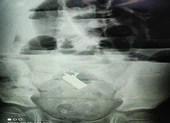

Trên phim chụp X-quang phổi cho thấy hình ảnh ứ khí phổi trái nên bác sĩ nghĩ đến khả năng bệnh nhi bị dị vật đường thở và đã tiến hành hội chẩn liên khoa.

Bệnh nhi được chỉ định nội soi phế quản. Trong quá trình làm thủ thuật, các bác sĩ phát hiện miếng hạt điều nhỏ ở cuối phế quản gốc trái và đã gắp ra thành công.